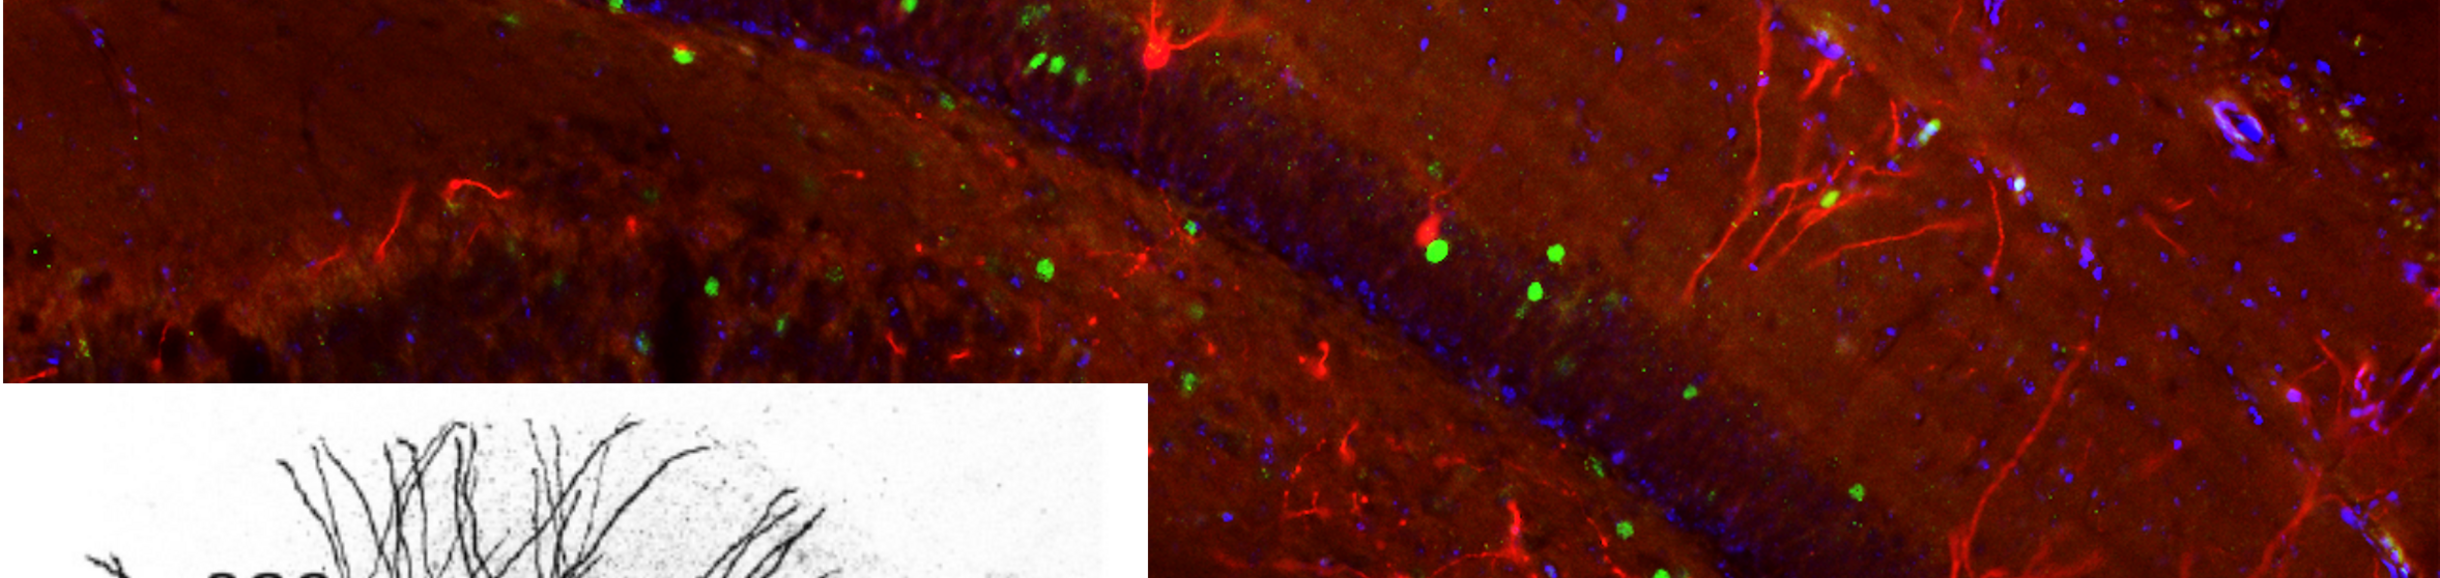

Description: The Santhakumar focuses on understanding circuit function of the hippocampal dentate gyrus and identifying processes contributing to neurological deficits after brain injury and epilepsy. Brain injury and epilepsy lead to neuronal loss and network reorganization which alter dentate function and lead to epilepsy and memory disorders. Our lab is examining multiple aspects of pathology from the role of circuit changes, neuro-immune interactions and altered birth of neurons epilepsy and memory disorders. We are currently examining an understudied subtype of neuron called semilunar granule cells which is thought to be involved in memory processing.

Project 1 will examine whether semilunar granule cells are preferentially activated in the memory task and abnormally activated after epilepsy. This will help understand the cellular basis for decreased and imprecise memory in epileptic patients. The study will involve the student inducing chemical epilepsy by drug injection in mice in which behavior-related neurons can be fluorescently labeled (TRAP mice) with a drug. Once animals develop epilepsy, the student will train control and epileptic mice in a memory task followed by injection of a chemical agent immediately after the behavioral task to tag active neurons. These mice will be sacrificed a week later and brain sections will be stained. The proportion of granule cells and semilunar granule cells will be quantified followed by statistical analysis to determine if the proportion of labeled semilunar granule cells is increased after epilepsy.

Project 2 will examine whether there is an increase in the number of semilunar granule cells born in epileptic mice. This will help understand how the dentate circuit changes in epilepsy and how this may contribute to seizures. The student will induce chemical epilepsy by drug injection in mice in which newly generated neurons can be fluorescently labeled by drug injection. Four weeks after the initial seizure and drug injection, mice will be sacrificed, brain sections prepared and stained to reveal the neurons generated during the drug-induced seizures. Sections will be imaged using a confocal microscope and number of granule cells and semilunar granule cells will be quantified.

Santhakumar Lab Image